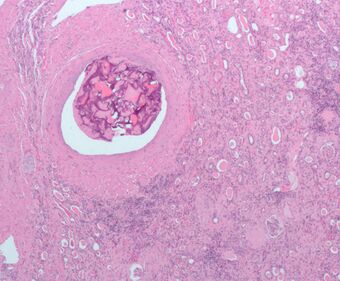

Micrograph of embolic material in the artery of a kidney. The kidney was surgically removed because of cancer. H&E stain.